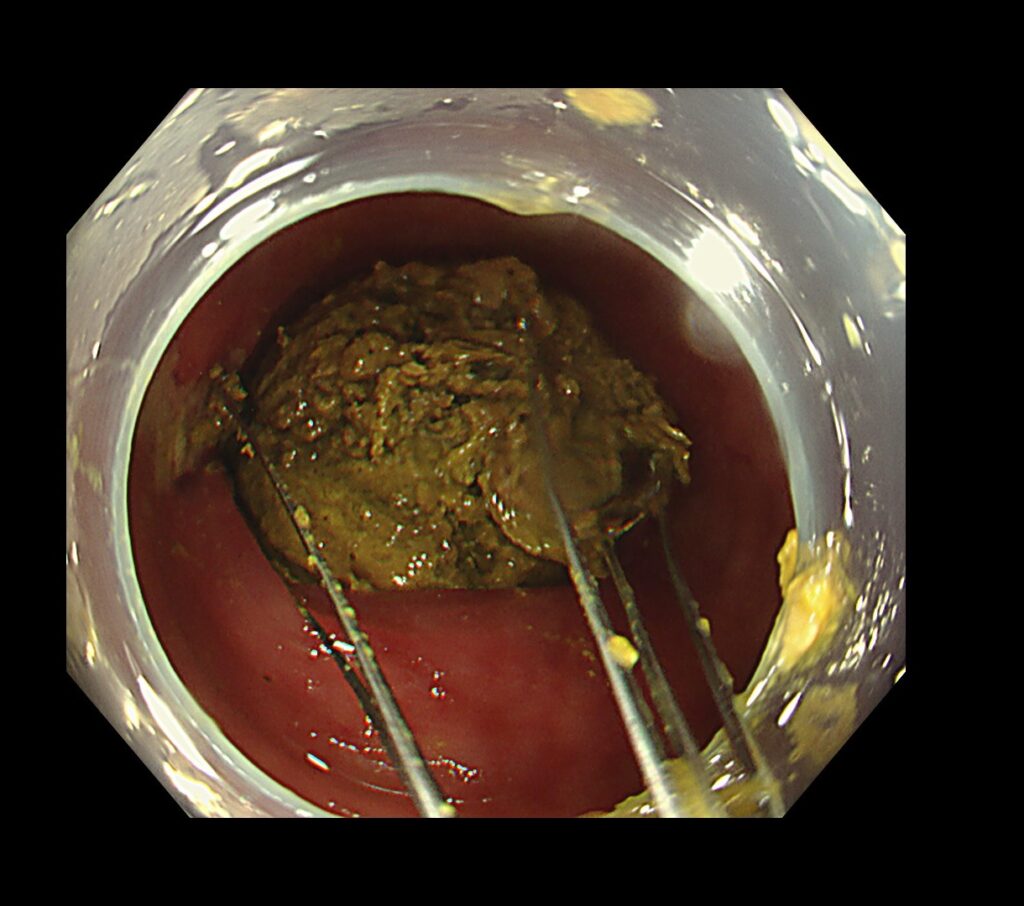

糞石による閉塞性大腸炎をきたしており、粘膜からの出血と腸に嵌頓する糞石を認めました。

糞石を内視鏡処置具で破砕していくと、何層にも重なり合う便の層を認めました。